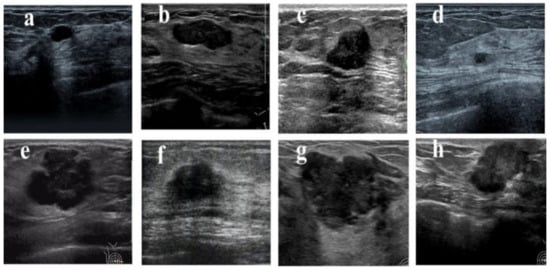

The 2D breast ultrasound images involved in this study were obtained from the Department of Ultrasonics, First Affiliated Hospital of Fujian Medical University, Fujian Province, China, with instrument models including Philips, Siemens, etc. The other color ultrasound diagnostic equipment has a probe frequency of 12 MHz. The study has passed the medical ethics review, complying with the principles of medical ethics and with consent from the patients involved. Ultrasound breast images of women aged from 14 to 80 years, collected between 2018 and 2021, were compared to pathological findings with a clear diagnosis. Among these, 418 were benign breast tumors and 373 were malignant breast tumors. Figure 5 shows the sample ultrasound images with benign and malignant breast tumors. In addition, the diagnosis of the images was verified by biopsy. The region of interest (ROI) of each breast ultrasound image was manually annotated by a radiologist with extensive experience and verified by another radiologist who has more than 10 years of breast ultrasound diagnosis experience. To protect the privacy of patients, the patient information around each breast ultrasound image has been removed.

Figure 5. Examples of breast ultrasound images in our datasets. (ad) are benign, (eh) are malignant.